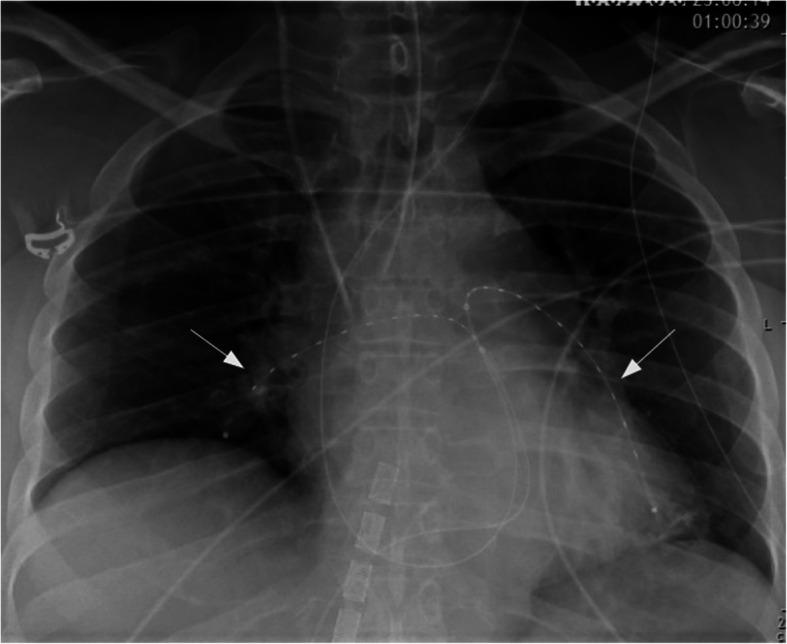

CASE PRESENTATION

We report two cases of high-risk perioperative PE. Both patients developed severe haemodynamic instability leading to cardiac arrest. After the implantation of a veno-arterial extracorporeal membrane oxygenation (ECMO), they were both successfully treated with USAT. Adequate improvement of right ventricular function was achieved; thus, ECMO could be successfully weaned after 3 and 4 days, respectively. Both patients showed favourable outcomes and could be discharged to rehabilitation.

病例报告

我们报告两例围手术期高危PE病例。两名患者均出现严重血流动力学不稳定,导致心脏骤停。在植入静脉-动脉体外膜肺氧合(ECMO)后,他们均成功接受了USAT治疗。右心室功能得到充分改善;因此,ECMO分别在3天和4天后成功撤机。两名患者均预后良好,可出院接受康复治疗。